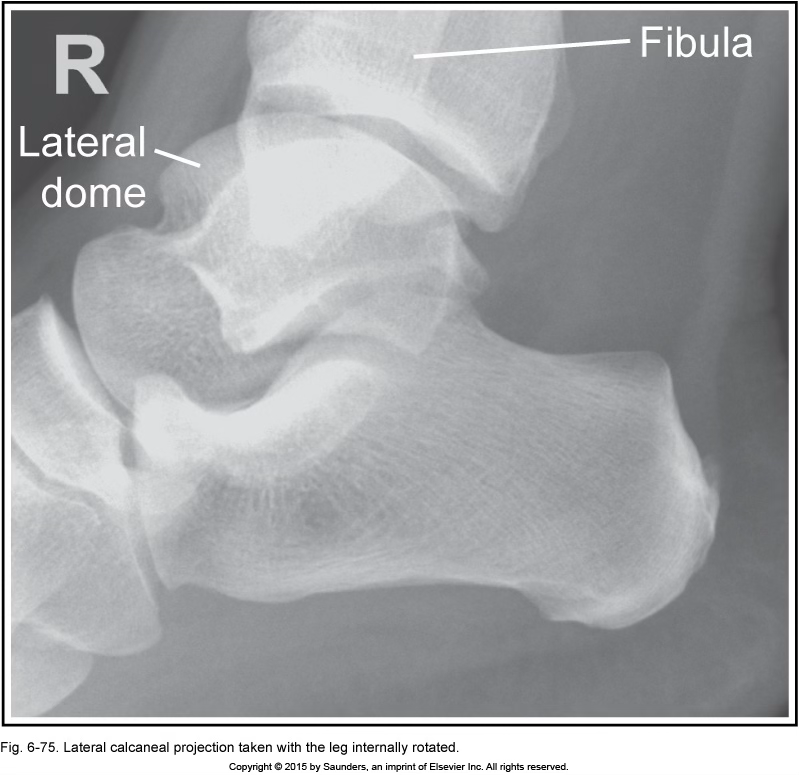

lateral calcaneus

leg internally rotated